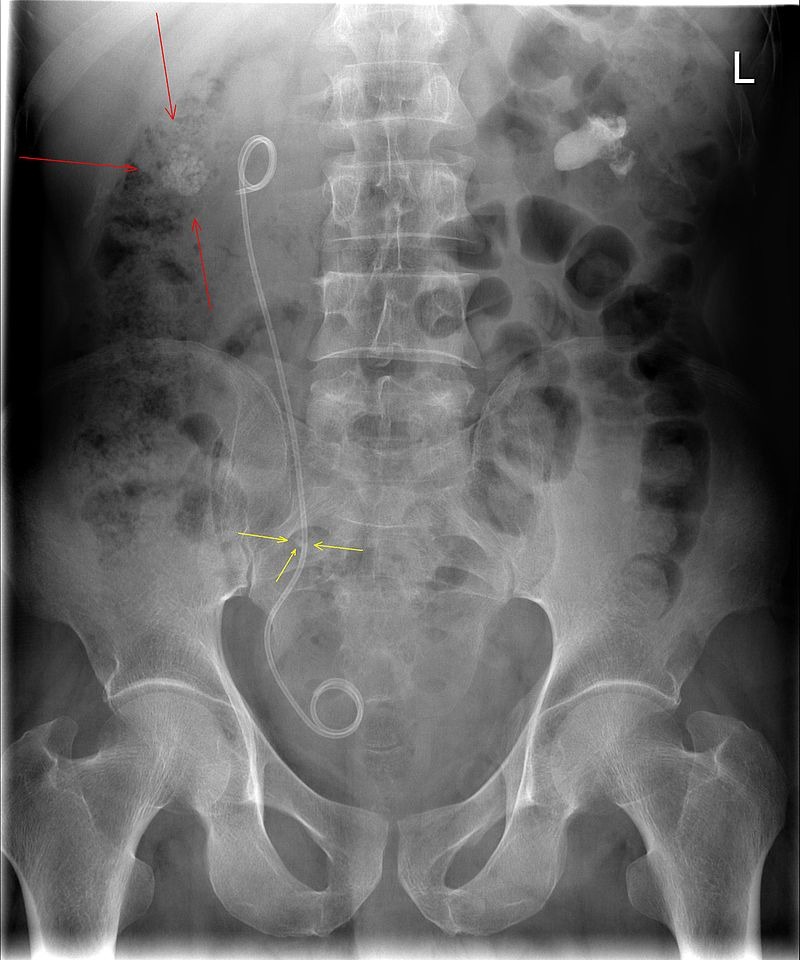

الدعامة الحالب:

عبارة عن أنبوب رفيع يتم إدخاله في الحالب لمنع أو معالجة انسداد تدفق البول من الكلى. يتراوح طول الدعامات بين 24 و 30 سم.

وتسمى أيضا دعامة الكلى السبب الأكثر شيوعًا للجوء لتركيب دعامات الحالب هو علاج حصى الكلى.